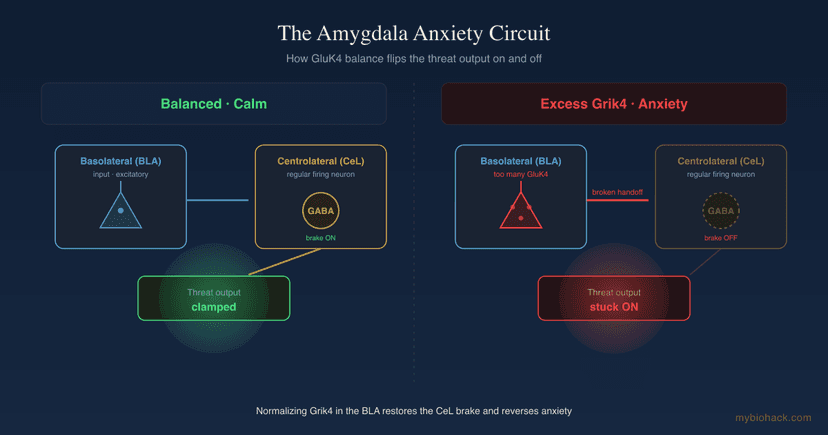

Brain Health

Grik4, The Amygdala, And The Glutamate Circuit Behind Anxiety

13 min read